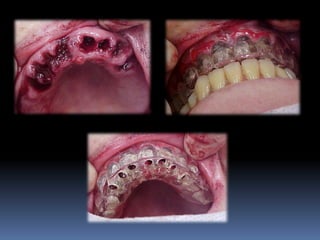

Modelos de estudo

Enceramento diagnóstico

Guia cirúrgica

Visão espacial do planejamento a

executar

•Articulados

•Projetar opções de terapêutica desde incisões,

delimitar áreas de reconstrução óssea,tipo de

prótese,número,distribuição, diâmetro dos implantes

•Compreensão do paciente

•Enceramento diagnóstico

•Guia cirúrgica